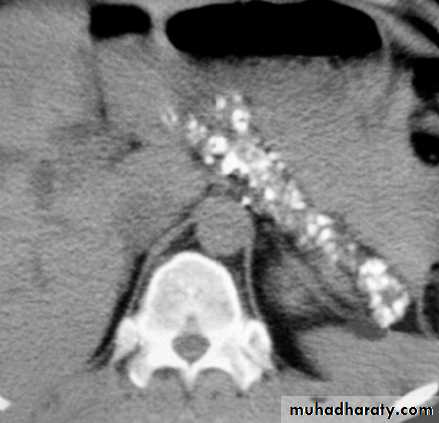

CT scan in chronic pancreatitis

CT

Ultrasonography

MRI, particularly MRCP